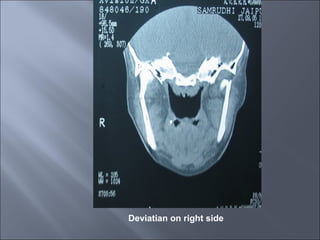

Deviatian on right side

Displaced condylar fracture

Displaced subcondylar # of R side